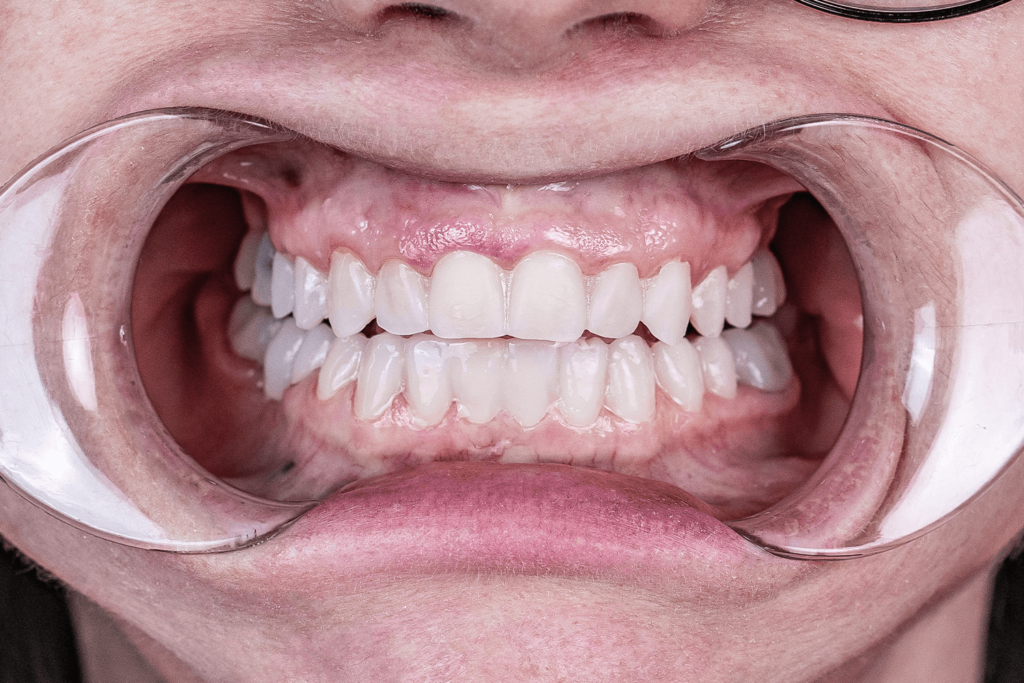

- покрыть зубы керамическими коронками и винирами и сразу поднять прикус ортопедическим методом.